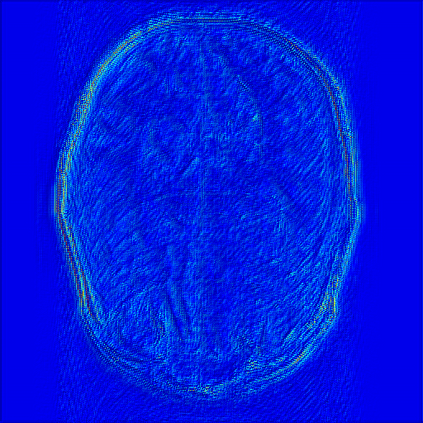

Reconstructing magnetic resonance (MR) images from undersampled data is a challenging problem due to various artifacts introduced by the under-sampling operation. Recent deep learning-based methods for MR image reconstruction usually leverage a generic auto-encoder architecture which captures low-level features at the initial layers and high?level features at the deeper layers. Such networks focus much on global features which may not be optimal to reconstruct the fully-sampled image. In this paper, we propose an Over-and-Under Complete Convolu?tional Recurrent Neural Network (OUCR), which consists of an overcomplete and an undercomplete Convolutional Recurrent Neural Network(CRNN). The overcomplete branch gives special attention in learning local structures by restraining the receptive field of the network. Combining it with the undercomplete branch leads to a network which focuses more on low-level features without losing out on the global structures. Extensive experiments on two datasets demonstrate that the proposed method achieves significant improvements over the compressed sensing and popular deep learning-based methods with less number of trainable parameters. Our code is available at https://github.com/guopengf/OUCR.